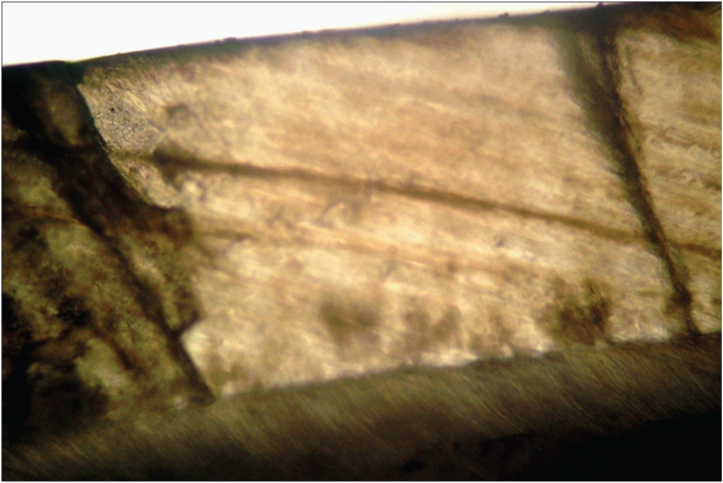

In [Table/Fig-8] intraoral periapical radiograph showing cervical resorption in relation to 33, 34, resorption in both cervical and apical region in relation to 35, 36. In [Table/Fig-9] intraoral periapical radiograph showing cervical and apical resorption in relation to 24, 25 and apical resorption in relation to 26. In [Table/Fig-10] intraoral periapical radiograph showing cervical and apical resorption in relation to 35, 36 and apical resorption in relation to 37. In [Table/Fig-11] intraoral periapical radiograph showing cervical and apical resorption in relation to 46, 47 and 48. In [Table/Fig-12] intraoral periapical radiograph showing cervical resorption in relation to 43, 44 and 45. [Table/Fig-13] Orthopantomograph. In [Table/Fig-14] lateral view of skull showing no osteogenic changes. In [Table/Fig-15] histological examination of extracted mobile teeth showing striae of Retzius, dentinal tubules and interglobular dentin with an area resembling dead tract. Correlating the history, clinical findings supported by radiographic appearance, diagnosis of Multiple Idiopathic external root resorption was made.

Histological examination of extracted mobile teeth showing striae of Retzius, dentinal tubules and interglobular dentin with an area resembling dead tract

[Table/Fig-16] showing the resorption of the roots of the extracted teeth in relation to 12, 41 and 42. The teeth having mobility were extracted. The teeth 12, 41 and 42 were sent for histopathological examination (ground sectioning) which revealed: crown morphology comprising of enamel and dentin. The enamel shows striae of retzius, dentin showed dentinal tubules, interglobular dentin with an area resembling dead tract (longitudinal section). [Table/Fig-17] showing the ground section of the extracted tooth specimen. Followed by removable partial denture and teeth with resorped root was endodontically treated. Patient was advised to maintain proper oral hygiene and referred to the department of periodontology for further treatment of gingival enlargement and periodic follow up was suggested.

Showing the ground section of the extracted tooth specimen